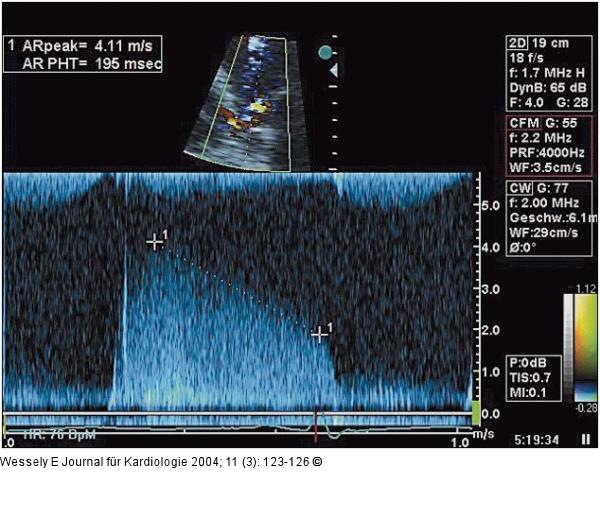

Abbildung 4: Aortenklappeninsuffizienz - Endokarditis CW-Dopplersignal der aortalen Regurgitation mit kurzer Druckhalbwertszeit |

CW-Dopplersignal der aortalen Regurgitation mit kurzer Druckhalbwertszeit |